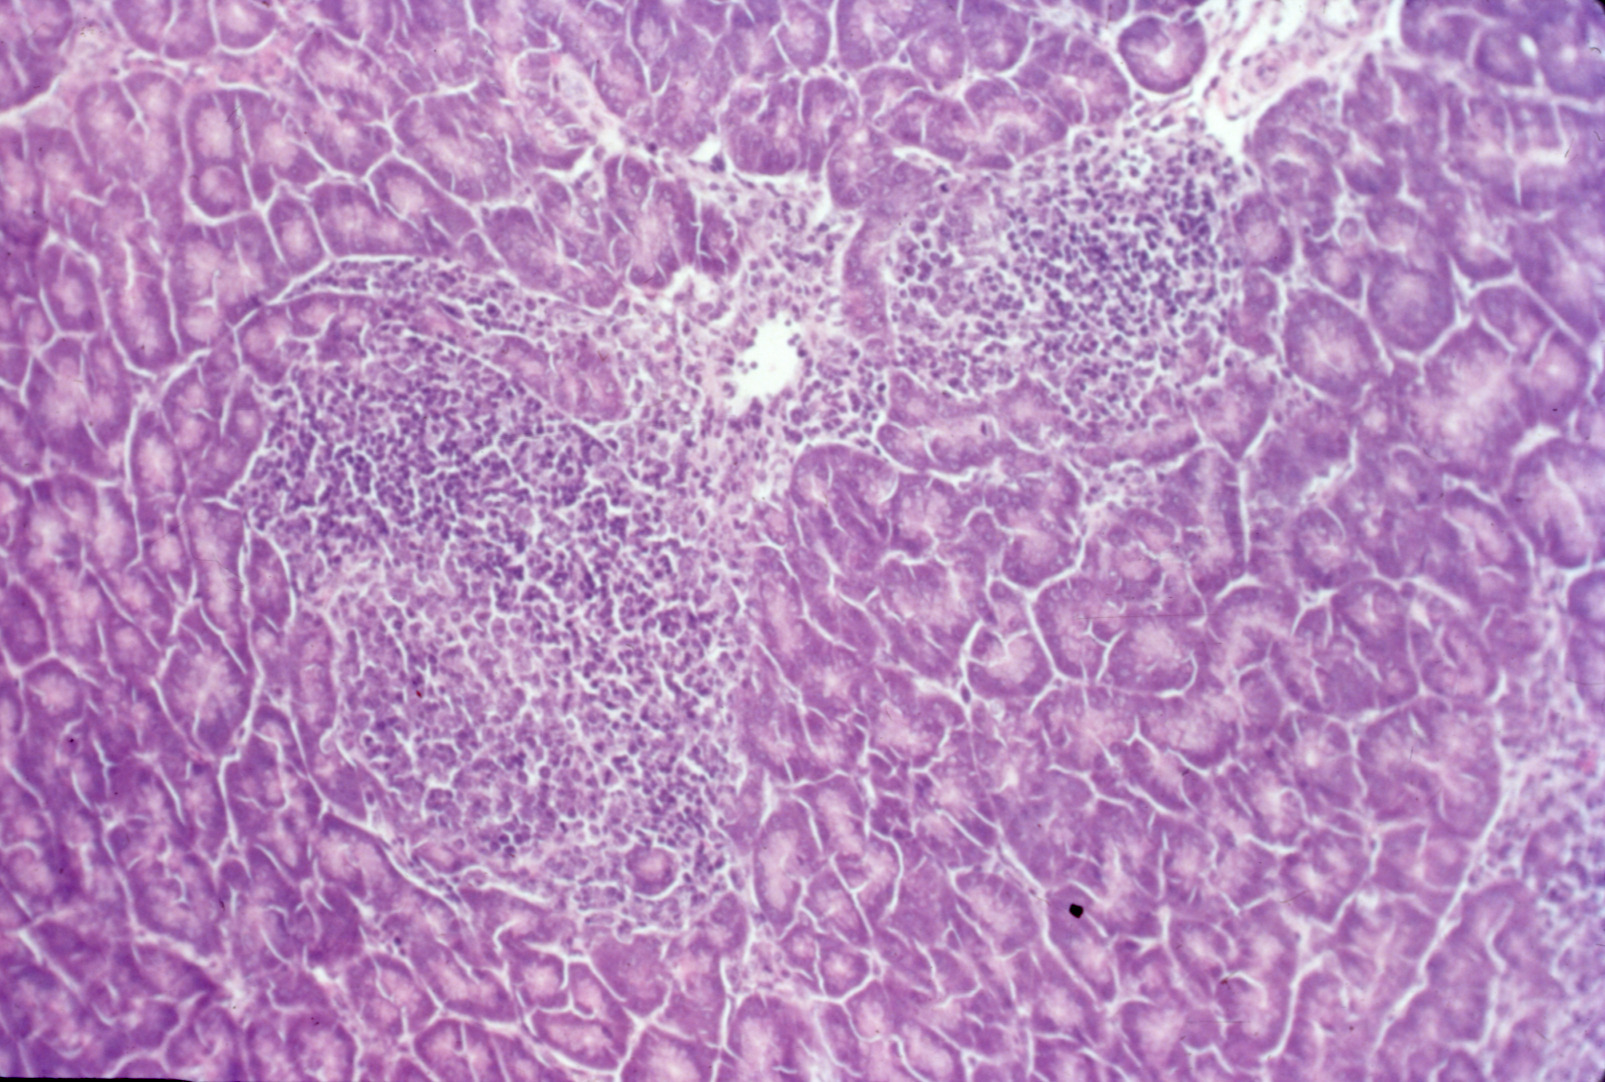

Avian encephalomyelitis (slide study set no. 5)

Avian encephalomyelitis Avian medicine Chickens--Diseases Turkeys--Diseases Pheasants--Diseases

Slide Study Set #5, Avian Encephalomyelitis, 2 sets (includes 32 color slides), 1974